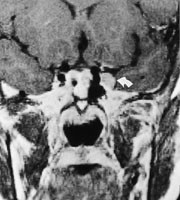

Cisternale lesjoner av abducensnerven gir isolert abduksjonsparese og forekommer ved økt intrakranialt trykk eller ved svulster i clivusområdet, som meningeom, kordom eller metastaser (fig 4). Abducensparese med hodepine er karakteristisk ved clivuskordomer. Svulsten vokser langsomt, og kan gi symptomer i form av intermitterende dobbeltsyn flere år før det er andre nevrologiske funn (11). Inflammatoriske tilstander i forbindelse med mellomørebetennelse kan bre seg til os petrosus og gi det klassiske bildet av Gradenigos syndrom, som ved siden av abducensparese består av ipsilateral facialisparese, ipsilaterale ansiktssmerter og nedsatt hørsel.